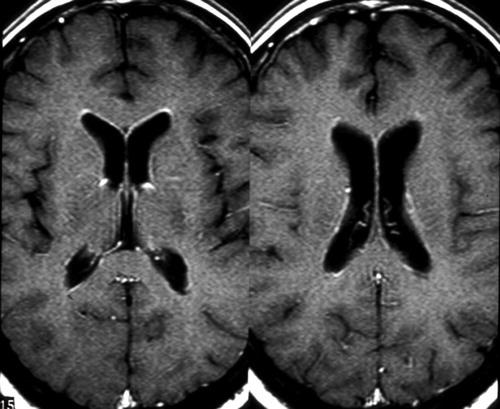

(а) МРТ, ДВИ, аксиальный срез: у пациента с пневмококковым менингитом определяются ограничение диффузии в III желудочке, а также детрит в боковых желудочках, обусловленные связанным с ними вентрикулитом. Визуализируется экссудат, локализованный в верхней мозжечковой цистерне, а также непротяженный участок субдуральной эмпиемы. Ценность ДВИ в диагностике вентрикулита невозможно переоценить.

(б) МРТ, постконтрастное Т1-ВИ, аксиальный срез: у того же пациента определяется гравитационно-зависимый уровень детрита в желудочках, наблюдается контрастирование как эпендимы, так и лептоменинкс.